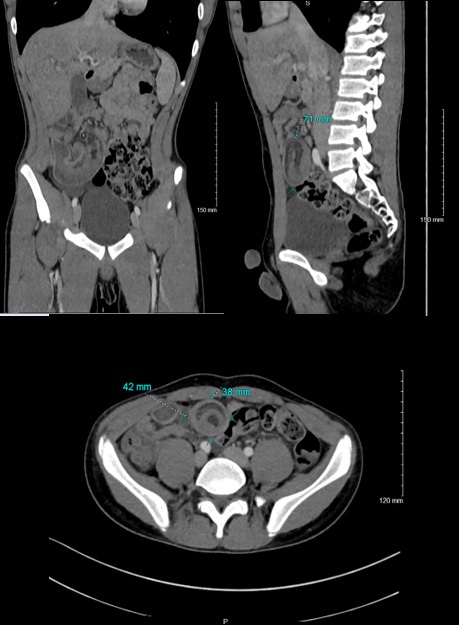

An abdominal computed tomography found the presence of an ileo-ileum intussusception in the right iliac fossa (the sausage 42 x 38 mm in diameter and 71 mm in length) whose content is a fatty image within the infiltration linked to the intussusception of the mesenteric fat, the presence of signs of early intestinal pain. Furthermore, there was no parietal enhancement defect, no identifiable underlying mass syndrome, but the presence of submillimetric nodal formations with the neighboring minor axis (Figure 3).

Figure 3: Ilio-ileum intussusception approximately 42x38 mm axially (a) and extended approximately 71 mm in length into the right iliac fossa (c). Greasy image within the infiltration linked to the invagination of the mesenteric fat. Moderate mesenteric infiltration and effusion blade in favor of signs of onset of pain (b).